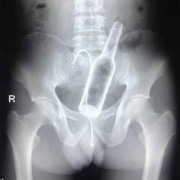

Можеби понекогаш се чувствувате виновно заради обилниот ручек што сте го изеле, но кога ќе видите што ставиле овие луѓе во својот стомак, ќе сфатите дека вие немате причина да се грижите. Барем не сте изеле батерии. Иако можеби имаат помалку калории, попрво би јаделе вкусни слатки со многу масти отколку киселински раствор. Луѓето имаат изедено некои многу чудни нешта…